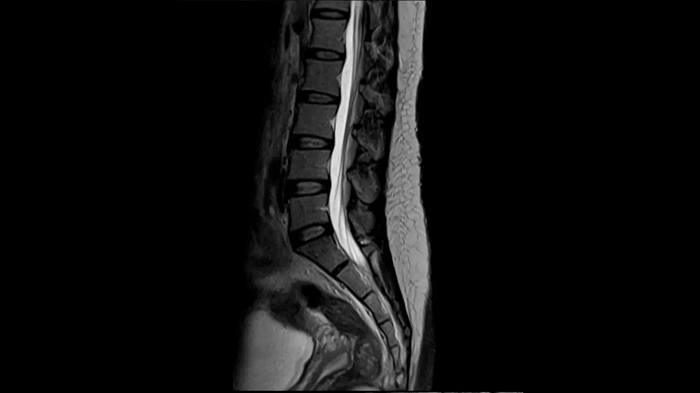

T2 TSE

Ideal depiction of the lower spine with T2 TSE imaging with the use of the Spine Coil.

Deep Resolve Gain & Sharp

0.4 x 0.4 x 4.0 mm2

TA 3:24 minutes

MAC-ID: 7aaaa0215.